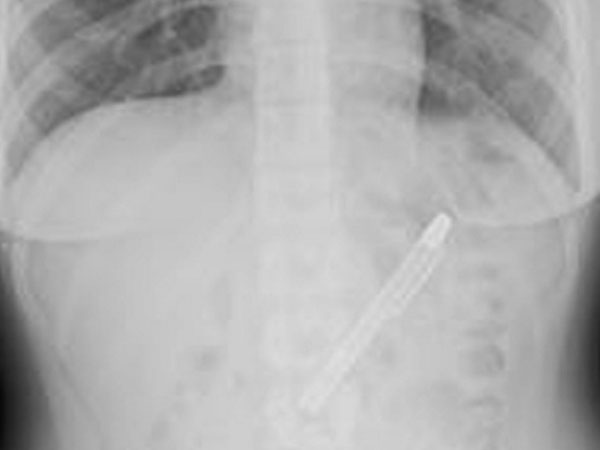

இதனால் உடனடியாக எக்ஸ்ரே எடுத்துப் பார்த்துள்ளனர் மருத்துவர்கள். அதில் ஷிங் வயிற்றுக்குள் இருப்பது ஒரு பேனா என்பது தெரிய வந்துள்ளது.

அச்சோதனையில் மருத்துவர்களே அதிர்ந்து போகும் அளவிற்கு நீளமான பொருள் ஒன்று ஷிங் வயிற்றுக்குள் இருந்துள்ளது தெரியவந்தது.